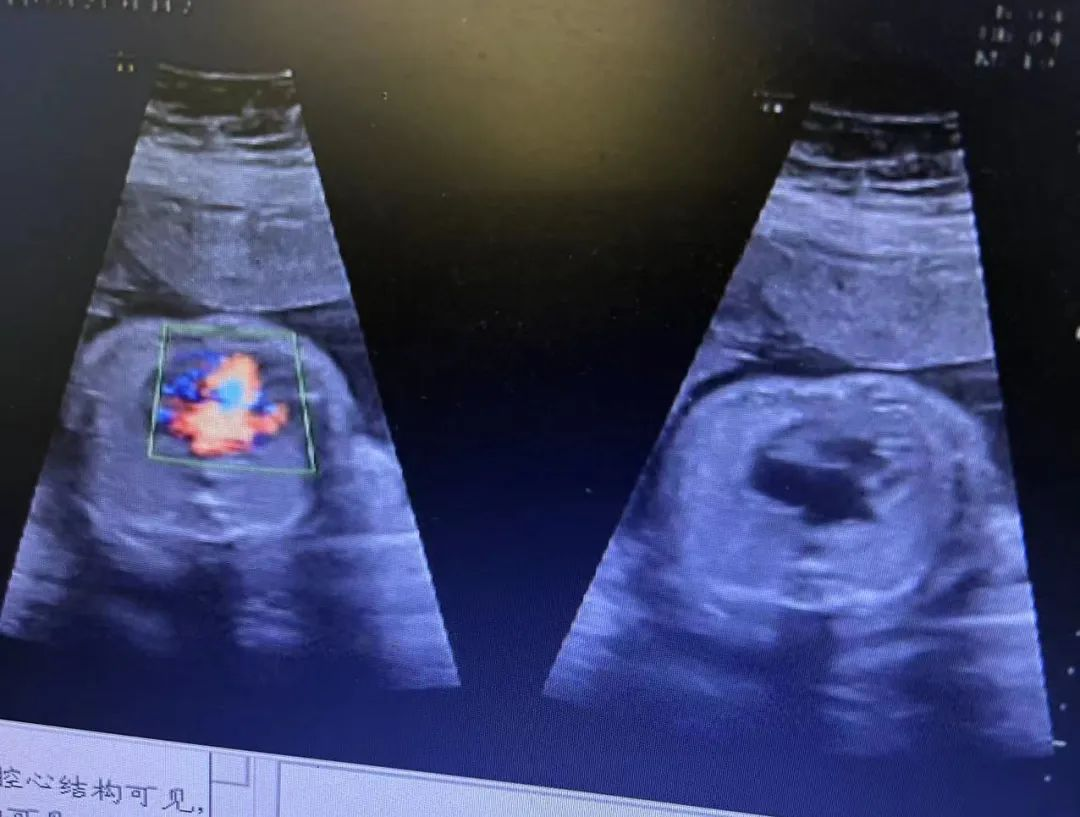

近日,武漢仁愛醫(yī)院收治了一例特殊的女患者。停經(jīng)數(shù)月才來醫(yī)院就診,發(fā)現(xiàn)自己懷孕,且經(jīng)過四維彩超產(chǎn)檢發(fā)現(xiàn)腹中胎兒心臟畸形。武漢仁愛醫(yī)院超聲科王娟主任介紹,由于該患者有多囊卵巢疾病病史,導(dǎo)致體態(tài)肥胖,足足有220斤,所以懷孕了都渾然不知,因停經(jīng)數(shù)月才想到來醫(yī)院看診,經(jīng)過檢查才發(fā)現(xiàn)自己已經(jīng)懷孕24周。

近日,我院超聲科醫(yī)生在給孕中期孕媽做四維彩超檢查時,發(fā)現(xiàn)胎兒查出異常,孕媽想留下這個寶寶,陷入了兩難。

武漢的劉女士(化名),前幾個月剛懷上寶寶,全家都特別高興。懷孕23周+時,劉女士在家人的陪伴下來到武漢仁愛醫(yī)院超聲科做了四維彩超檢查,當(dāng)醫(yī)生拿出檢查報告的時候,劉女士卻當(dāng)場傻眼了,原來,在四維彩超的報告里,診斷出了胎兒右肺囊性腺瘤樣病變,她的心頓時揪了起來!

劉女士看到檢查結(jié)果后,擔(dān)心該病變會影響腹中寶寶的健康,考慮是否應(yīng)該終止妊娠。隨即,武漢仁愛醫(yī)院超聲科王娟主任為劉女士耐心地解釋:“先天性肺囊腺瘤是一種肺組織錯構(gòu)畸形,先天性肺囊腺瘤畸形病例約70%的腫塊大小較穩(wěn)定;約20%腫塊產(chǎn)前明顯縮小或消失;僅10%腫塊是進(jìn)行性增大。單純的先天性肺囊腺瘤(CCAM)無水腫的胎兒可以密切隨訪,在28周前接受連續(xù)超聲復(fù)查,CVR<1.6,一般超聲動態(tài)監(jiān)測2~4周監(jiān)測一次,而對于CVR≥1.6的需要在28周前每周1-2次的超聲監(jiān)測,防止出現(xiàn)胎兒水腫,直到分娩。”